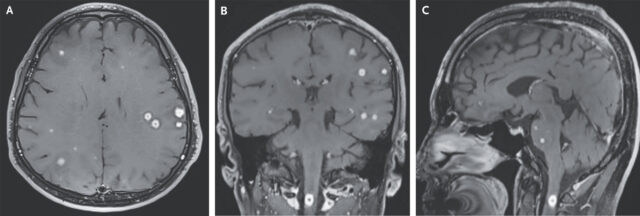

Magnetic resonance imaging (MRI) of the head with gadolinium enhancement revealed numerous small, spherical, peripherally enhancing nodules in the cerebral hemispheres (Panels A and B), basal ganglia, cerebellum, and brain stem, as well as in the upper spinal cord with surrounding edema (Panel C).

The man had previously been treated for the infection in his lungs but came into the hospital’s emergency department after two weeks of unexplained headaches, neck pain, and tingling in his right hand. The MRI and Computed-Tomography (CT) scans clearly revealed the problem: rare nodules and lesions, called tuberculomas, speckling his lungs and central nervous system, including both cerebral hemispheres, the basal ganglia deep inside the brain, the cerebellum at the back of the brain, the brain stem, and the upper spinal cord.